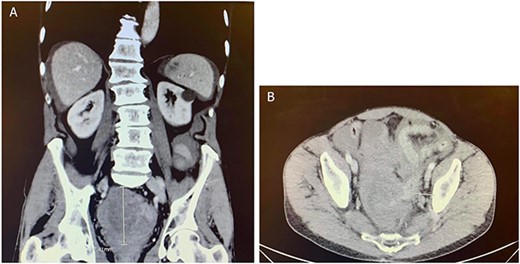

Two months after the tumor was grossly resected and 1 month into Imatinib treatment, the patient presented to the Emergency Department with complaint of abdominal discomfort, constipation and nausea. CT abdomen and pelvis noted mid small bowel distention, suggestive of partial small bowel obstruction with mild ascites. Importantly, a mass-like focus measuring 5 × 3.8 cm was found in the pelvis anterior to the rectosigmoid junction (Fig. 3). A nasogastric tube was subsequently placed and the patient was administered empiric antibiotics. Considered a failure of conservative management, the patient was taken to the operating room again for an exploratory laparotomy, lysis of adhesions and debulking of the mass. The patient tolerated the procedure well with no complications. The patient maintained a typical postoperative course and was discharged with oncological follow-up and continued Imatinib treatment. On 2 and 4 months follow-up CT, the pelvic mass measured 4.1 × 3.3 and 2.6 × 2.7 cm (Fig. 4), respectively.

CT abdomen and pelvis with contrast identified small bowel distention and a mass-like focus measuring 5 × 3.8 cm in the pelvic region.